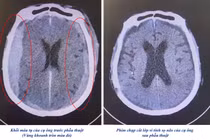

Sau phẫu thuật, bệnh nhi dần ổn định. Sau 3 ngày, bệnh nhi chụp CT kiểm tra lại cho thấy khối máu tụ gần như đã được lấy hết, đồng thời tỉnh táo hoàn toàn, đã ngồi dậy đi lại được. Đến ngày thứ 7, bệnh nhi đã được ra viện.